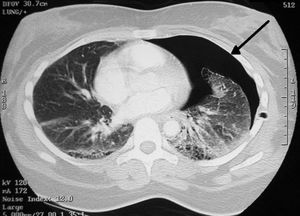

흉부 CT을 통해 비교적 큰 낭포라면 위치를 확인할 수 있다.[72] 폐기포를 정확히 확인하기 위해 흉부 CT를 실시한다.[15] CT 스캔은 기흉의 크기를 보다 정확하게 결정할 수 있지만, 이 상황에서 루틴하게 사용하는 것은 권장되지 않는다.[33]